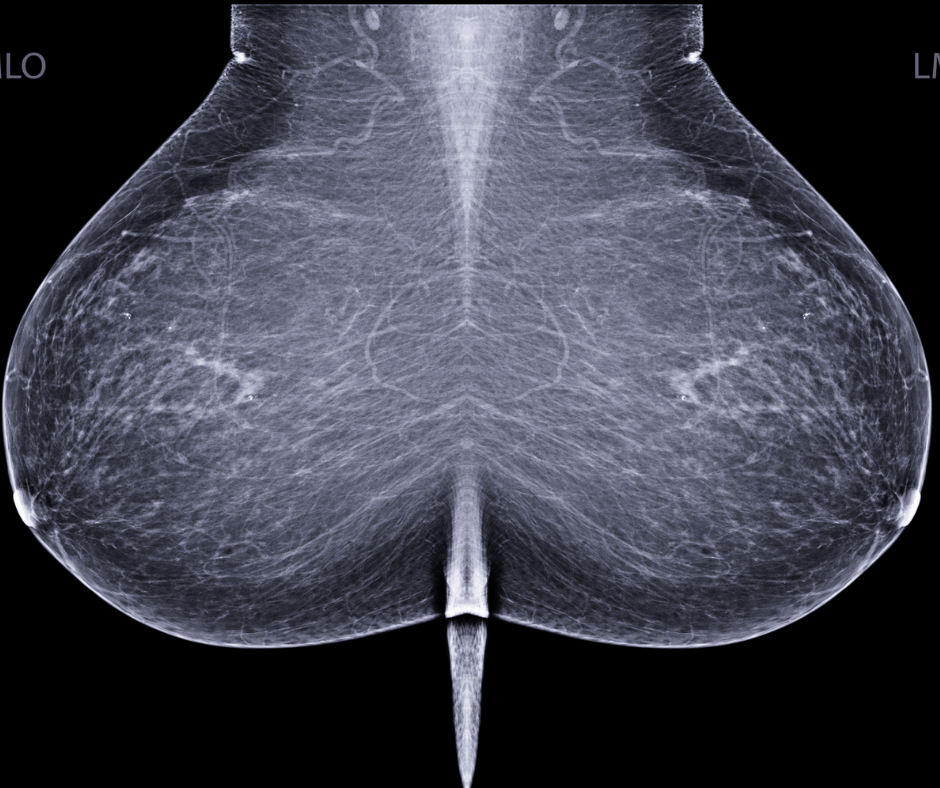

Artificial intelligence (AI) software assigned high malignancy risk scores to mammography exams completed up to two years prior to breast cancer diagnosis in over 38 percent of screen-detected cancer cases and over 39 percent of interval cancer cases, according to newly published research.